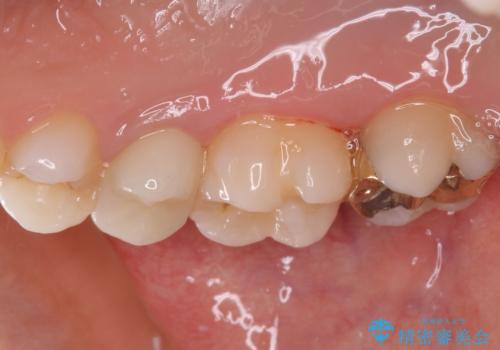

海外転居前にむし歯を治療したい 精密なむし歯治療

- 近々海外へ転居するとのことで、事前に処置をしておくべきむし歯がないか、気にして来院された患者様です。

レントゲン写真などから、速やかに処置を行うべき歯が2歯あったため、それぞれセラミックインレーとPGAインレー(ゴールドインレー)にて修復治療を行うこととしました。

どちらの歯も痛みなどの症状はなく、治療後も異常所見なく経過をたどっています。

上顎大臼歯は向かい合った人から見えることはほとんどないため、切削量が少なく、適合の良いゴールドインレーが大変おすすめとなります。